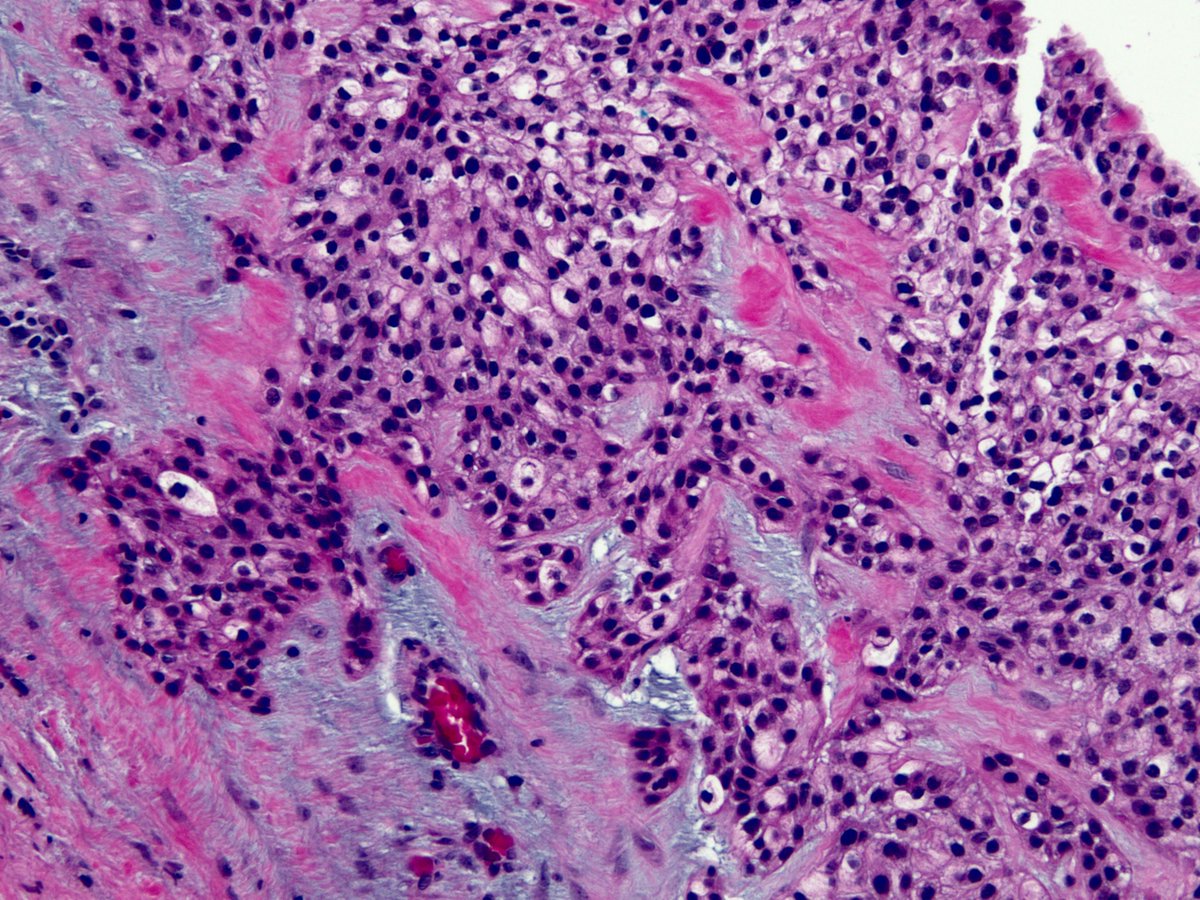

Ulcerated Anal Amelanotic Melanoma in 60y/M. #APCON2022 #APCON2022PathTweet GI James Padma Priya J Kenny De Gracia T. Archana bhat Aditya Agnihotri 🇮🇳 Vijay Shankar S Annie A. Wu, MD, PhD Olaleke Folaranmi Daisy Maharjan Dante Aswathy Menon Ananthvikas Dr Anila Sharma Frank Ingram, MD Arunima Deb, MD #pathology #PathTwitter